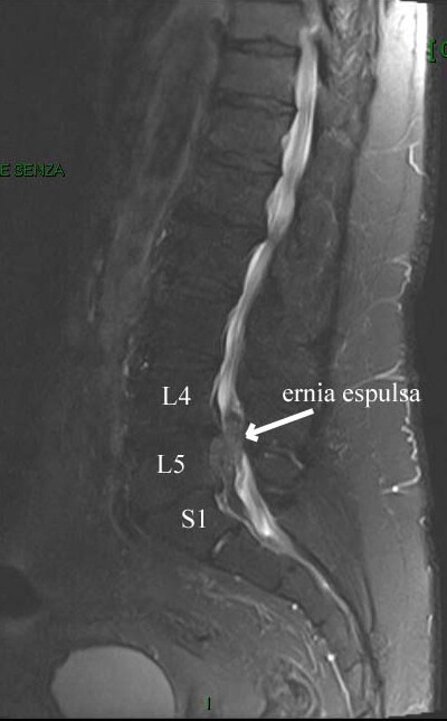

Il signore presentava intensa lombalgia e sciatalgia destra intensa e invalidante, tale da costringerlo a letto, con grave disagio di ogni attività sociale e impossibilità assoluta a svolgimento dell'attività lavorativa.

Nella scala soggettiva del dolore [VAS] che va da 0 (assenza di dolore) a 10 (dolore insopportabile e estremamente intenso), il signore riferiva una iniziale VAS di 8-9.

Gli veniva prescritta esecuzione di risonanza magnetica della colonna lombare. Effettuava alcune sedute di scramblertherapy, con associata terapia antidolorifica e anti-infiammatoria. La VAS (il dolore) migliorava e scendeva da 8-9 a 6-7.

Ciò consentiva una più agevole esecuzione della risonanza magnetica, che evidenziava una voluminosa ernia discale espulsa L5-S1 destra.

Eseguiva 15 sedute di ozonoterapia eco guidata sulla focalità erniaria.

La regressione del dolore è stata lenta e progressiva, con graduale discesa della VAS a 0-1.

Il signore beneficiato di un recupero del contesto familiare, ha potuto riprendere la normale attività lavorativa e sociale e sportiva non agonistica.

A distanza di 4 mesi ha effettuato una nuova risonanza magnetica lombare, che ha documentato la completa scomparsa della voluminosa ernia.

Secondo i criteri della medicina moderna non si può affermare con assoluta certezza che l’ozonoterapia eco guidata sia stata la causa diretta ed esclusiva della scomparsa dell’ernia, tenendo anche conto che la regressione di un’ernia discale può essere un fenomeno naturale e spontaneo.